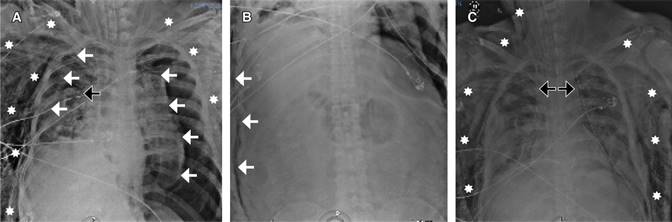

El caso que se presenta es el de un hombre de 42 años de edad, hospitalizado en la Unidad de Terapia Intensiva de Adultos (UTIA) por choque séptico y disfunción orgánica múltiple secundario a un absceso profundo de cuello ya drenado quirúrgicamente y con desarrollo de Klebsiella pneumoniae en cultivos del material purulento obtenido del absceso, hemocultivo, urocultivo y cultivo de secreción bronquial. El manejo brindado en la UTIA fue con base en paquetes, recomendaciones y metas de la campaña para incrementar la supervivencia en sepsis, con soporte multiorgánico, hemodiálisis intermitente por lesión renal aguda y ventilación mecánica invasiva por síndrome de insuficiencia respiratoria aguda grave (Figura 1). En su día siete de estancia en la UTIA con soporte mecánico ventilatorio invasivo en modo controlado con fracción inspirada de oxígeno (FiO2) al 60%, presión positiva al final de la espiración (PEEP) 10 cmH2O, frecuencia respiratoria de 18/minuto, presión control (PC) de 20 cmH2O, presentaba con estos parámetros una saturación por oximetría de pulso de 91% y relación PaO2/FiO2 160 mmHg. Desarrolló súbitamente incremento en las presiones de la vía aérea con desaturación progresiva, inestabilidad hemodinámica y aumento de volumen en el tórax anterior bilateral, presencia de crepitación a la palpación del tórax y abdomen, y disminución de ruidos respiratorios en ambos campos pulmonares a la auscultación. En rastreo ultrasonográfico del tórax con signo de «código de barras» en ambos hemitórax, por lo que se colocó de manera inmediata sonda endopleural en el hemitórax derecho percibiendo fuga aérea inmediata con mejoría parcial de la oxigenación por oximetría de pulso (SpO2 75%) e incremento en los parámetros de presión arterial media (PAM 50 mmHg). En la radiografía simple portátil del tórax con imagen de pneumotórax bilateral con reexpansión parcial del parénquima pulmonar derecho y pnemotórax izquierdo, por lo que se colocó otra sonda endopleural en el hemitórax izquierdo mejorando tras dicha intervención la SpO2 al 96% y la TAM a 70 mmHg. En control radiográfico simple, con reexpansión del parénquima pulmonar bilateral e imagen en relación enfisema subcutáneo extenso (grado V) (Figura 2A-C), por lo que se decidió realizar incisiones cutáneas infraclaviculares con disección roma subcutánea hasta la fascia pectoral mayor bilateral y colocación de drenajes de tipo BioVac, con lo cual se logró la resolución del enfisema subcutáneo en 24 horas (Figura 3). Se retiraron los drenajes BioVac 48 horas posteriores a su colocación sin recurrencia del enfisema subcutáneo.

Figura 2: Secuencia de radiografías simples (portátiles) de tórax. A) Flechas blancas delimitan borde de parénquima pulmonar colapsado; asteriscos blancos demarcan la distribución de imagen radiolúcida secundaria a enfisema subcutáneo; flecha negra: señala la punta de sonda endopleural en hemitórax derecho. B) Flechas blancas demarcan la imagen radiolúcida secundaria a enfisema subcutáneo en el trayecto de toda la pared abdominal. C) Flechas negras señalan la presencia de sonda endopleural en ambos hemitórax con adecuada reexpansión del parénquima pulmonar; asteriscos blancos señalan la distribución de imagen radiolúcida secundaria a enfisema subcutáneo.

Figura 3: Radiografía simple (portátil) de tórax. Flechas negras señalan la presencia de drenajes subcutáneos de tipo BioVac en área infraclavicular y subcutánea. Se aprecia estatus de sonda endopleural en ambos hemitórax con adecuada reexpansión del parénquima pulmonar. Asterisco blanco señala el área limitada de imagen radiolúcida secundaria a enfisema secundario 24 horas posteriores a la colocación de los drenajes subcutáneos tipo BioVac.